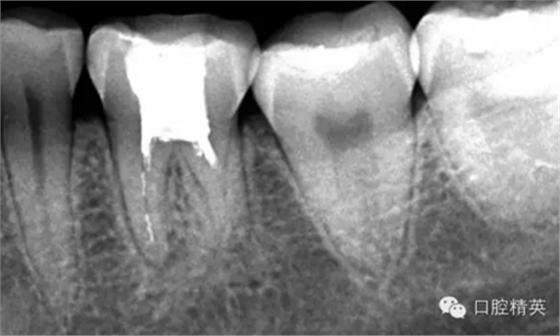

這個病例難以疏通在于根中上段堵塞,根尖下段有臺階的形成,感覺不到彎曲的方向。首先我們處理根上段,我們可以采取的方法是先預備跟中上段,將它擴開來,這樣有利于根尖下段的預備,建立良好的視野。對于根尖下段的臺階和彎曲 ,8號挫預彎,第二步要知道根管彎曲的方向,沿著根管彎曲的方向疏通。特別是有臺階的地方,一定不要硬來,慢慢旋轉(zhuǎn)找到根管彎曲的方向(結(jié)合x線片)避開臺階,一定要記住慢慢旋轉(zhuǎn)角度越小越好,正旋逆旋找“緊點”,有經(jīng)驗的醫(yī)生大概都知道,找到了“緊點”就等于找到了希望。手法一定要輕柔不易暴力!切記切記!戒浮戒躁(這句話也是特別要告訴我自己)。

近頰為疏通。慢慢找點可下,近頰花費一小時。

近中兩根試尖,預備根管15分鐘。

近中兩根根充。

這個病例主要是針對臺階的疏通方法,感覺好像很抽象很飄渺。因為這些都是要看自己的手感和很多細節(jié)的注意。特別是旋轉(zhuǎn)的角度不宜過大,一點一點的找可以避開臺階的道路。